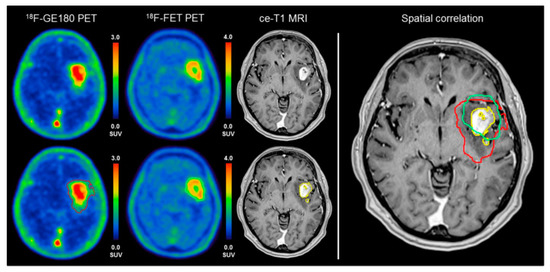

- Unterrainer, M.; Fleischmann, D.F.; Diekmann, C.; Vomacka, L.; Lindner, S.; Vettermann, F.; Brendel, M.; Wenter, V.; Ertl-Wagner, B.; Herms, J.; et al. Comparison of 18F-GE-180 and dynamic 18F-FET PET in high grade glioma: A double-tracer pilot study. Eur. J. Nucl. Med. Mol. Imaging 2019, 46, 580–590. [Google Scholar] [CrossRef]